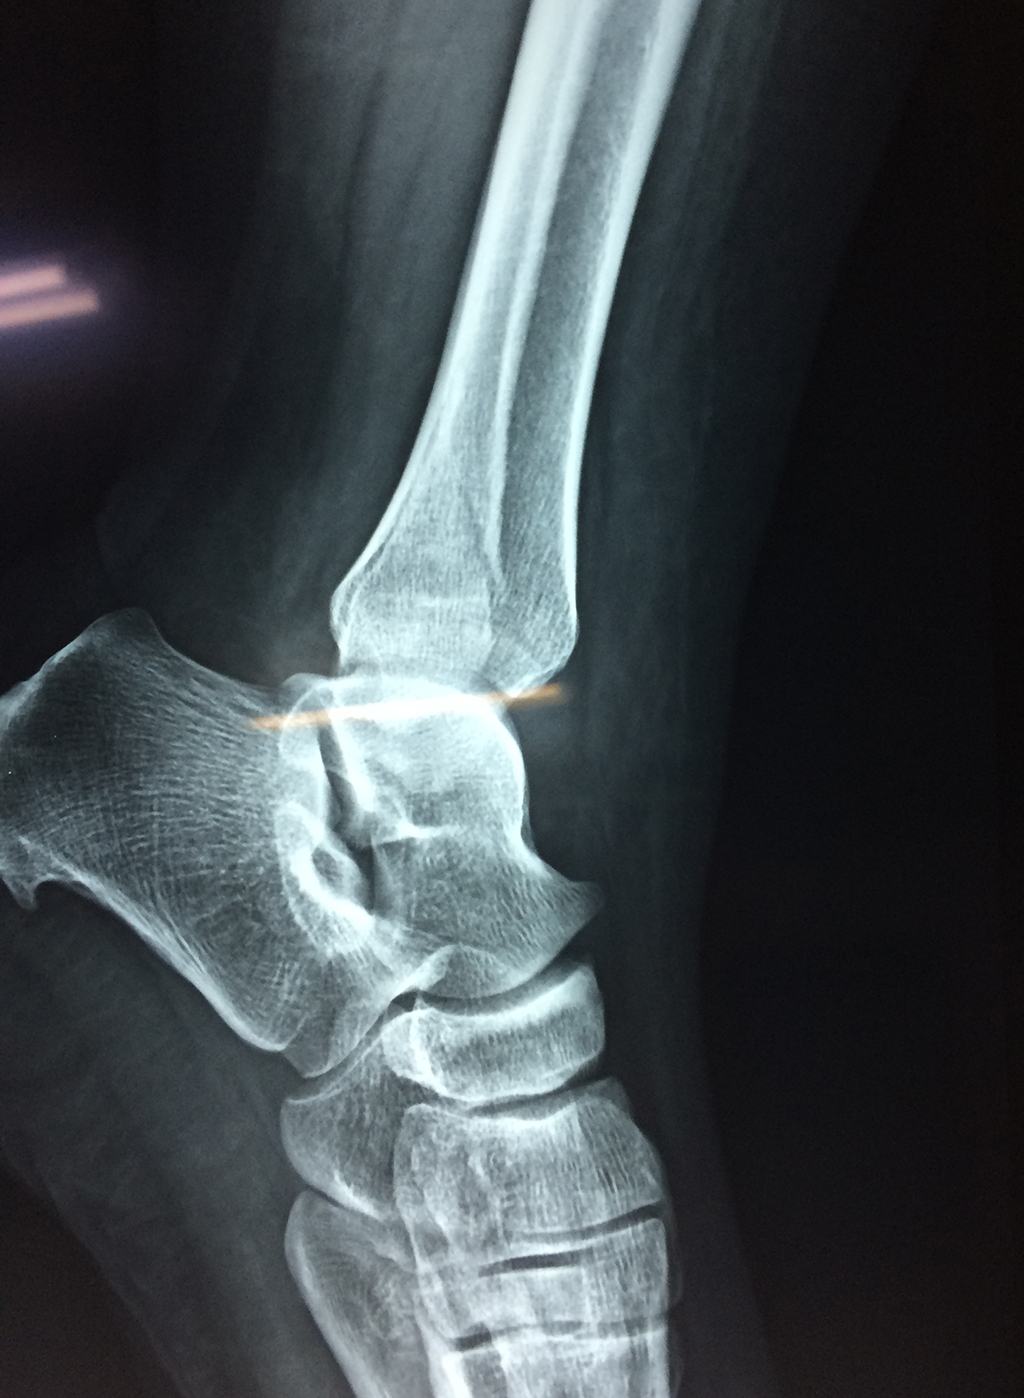

Una fractura de tobillo es la rotura de uno o más de los huesos del tobillo. Estas fracturas pueden ser:

Algunas fracturas de tobillo pueden requerir cirugía si:

- Los extremos de los huesos están desalineados entre sí (desplazados).

- La fractura se extiende hasta la articulación del tobillo (fractura intra-articular).

Cuando se necesita cirugía, es probable que esta implique el uso de clavijas de metal, tornillos o placas para sostener los huesos en su lugar mientras la fractura se consolida. Los elementos de soporte pueden ser temporales o permanentes.